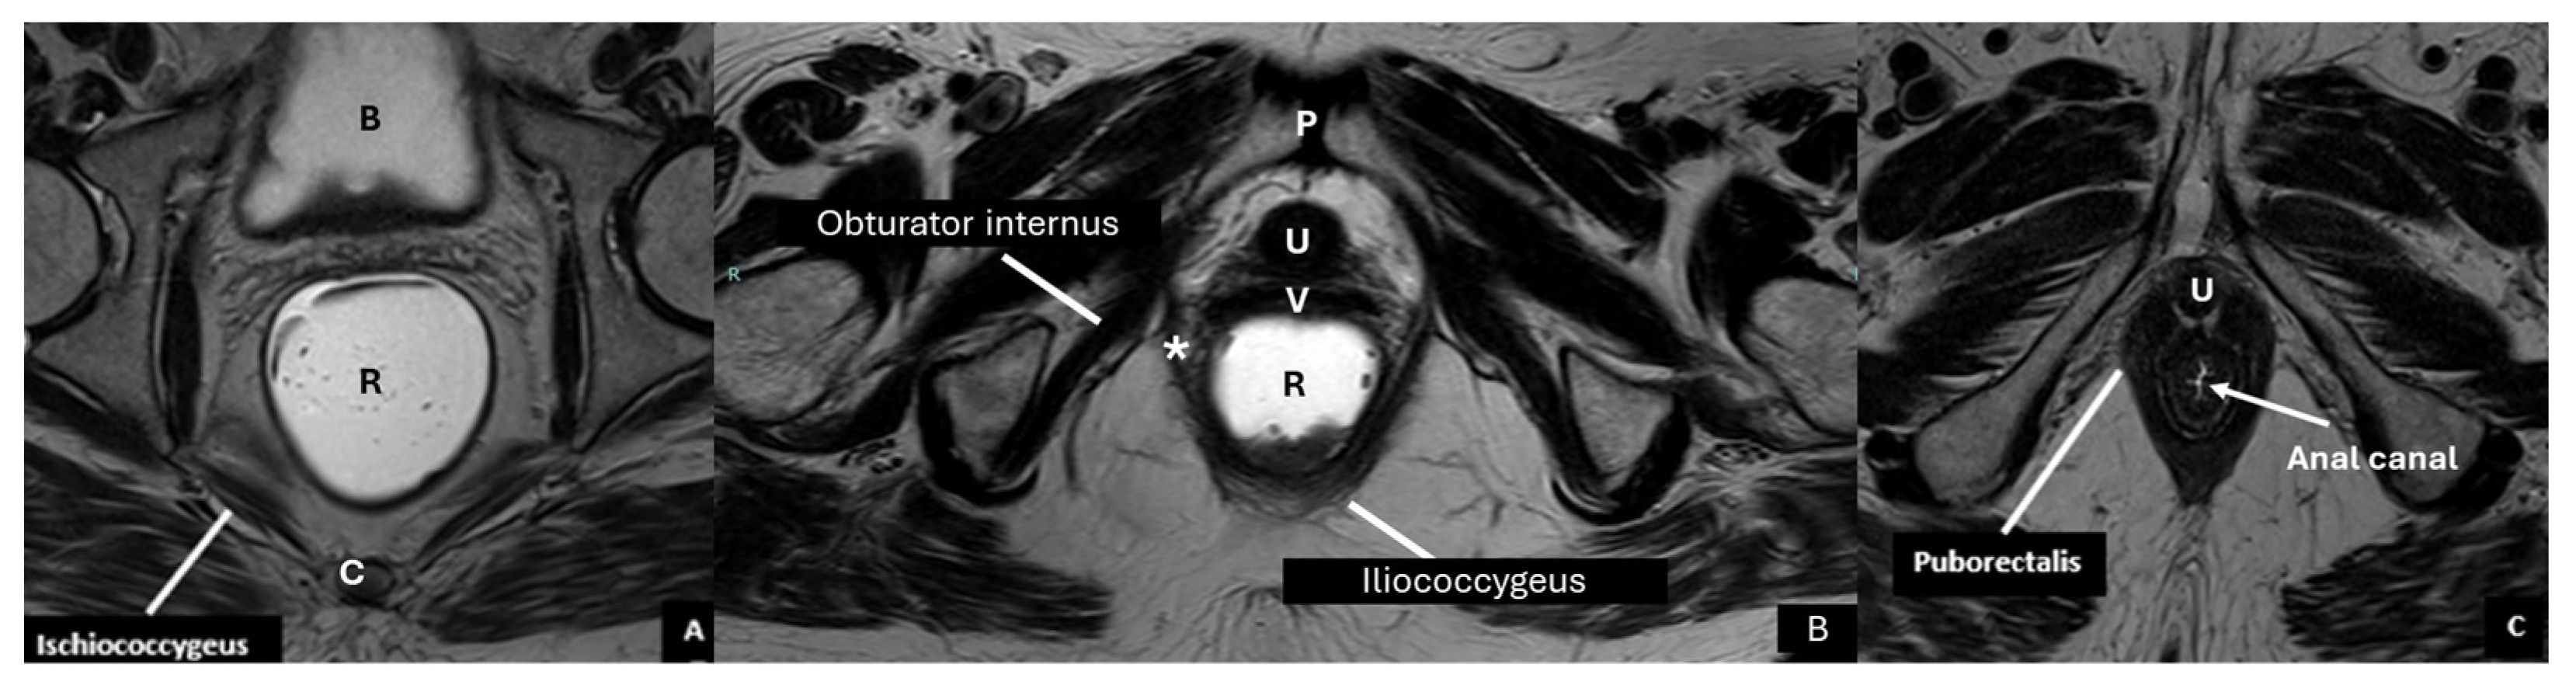

- Guo, M.; Zbar, A.P.; Wu, Y. Imaging the levator ani and the puborectalis muscle: Implications in understanding regional anatomy, physiology and pathology. Scand. J. Gastroenterol. 2023, 58, 1295–1308. [Google Scholar] [CrossRef] [PubMed]

| Pelvic diaphragm | Composed of ischiococcygeus, iliococcygeus, pubococcygeus, and puborectalis | Forms the levator ani, maintains pelvic support |